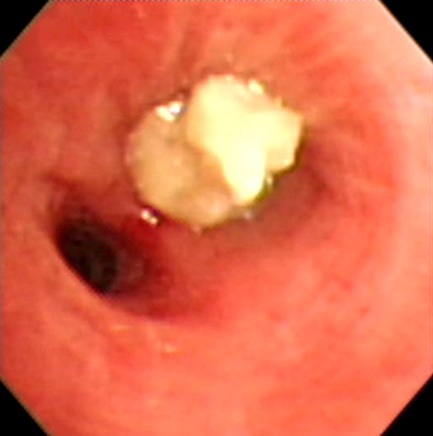

F/27

C.C : 2°³¿ù ÀüºÎÅÍ ¹Ýº¹µÇ´Â cough, sputum, rhinorrhea.

P/Ex. : wheezing on both lower lung fields.

Chest PA, Chest CT, Bronchoscopy , M-test was done.

Methacholine bronchial challenge test (+)